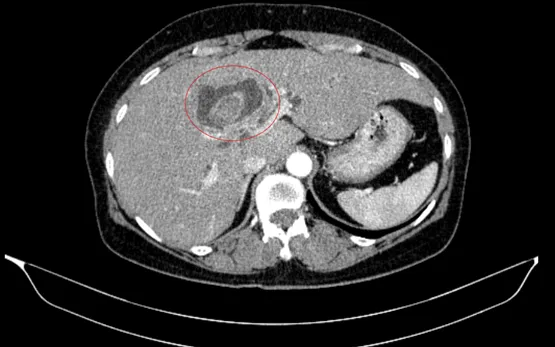

Bệnh nhân nữ, 59 tuổi, nhập viện trong tình trạng vàng da, ngứa và đau vùng hạ sườn phải kéo dài. Kết quả chẩn đoán hình ảnh ban đầu cho thấy tổn thương đường mật trong gan kèm sỏi và tình trạng giãn đường mật.

Cụ thể, ung thư đại tràng phải được xác định ở giai đoạn sớm (IA), chưa có di căn hạch. Trong khi đó, ung thư đường mật trong gan ở giai đoạn tiến triển (IIIB), có xâm lấn và di căn hạch.

Ca phẫu thuật bao gồm cắt đoạn đại tràng phải kèm nạo vét hạch D3, đồng thời cắt gan trái và đường mật ngoài gan để xử trí tổn thương đường mật.